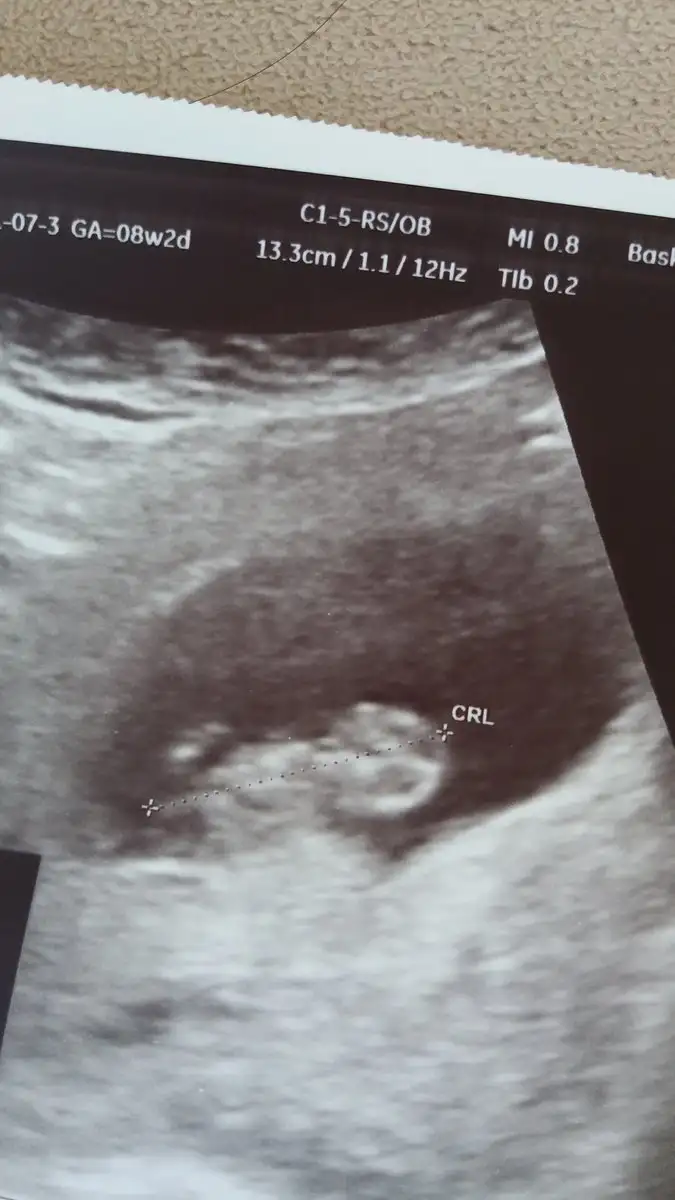

HR canimMerhaba kizlar size bir sorum olacakti. Ultrason kadiginda kalp atisini veya hizini gosteren bir terim, ifade vs.. varmidir? Var ise bunu nasil ogrenebiliriz

Da hr 178 bpm yaziyor benimkindeMerhaba kizlar size bir sorum olacakti. Ultrason kadiginda kalp atisini veya hizini gosteren bir terim, ifade vs.. varmidir? Var ise bunu nasil ogrenebiliriz

Gözün aydın maşallah bebeğineKızlar minigimizi gördük kalp atışını duyduk çok şükürdarisi tüm bekleyenlere inşallah görünce o kadar heyecanlandım o kadar mutlu oldum ki